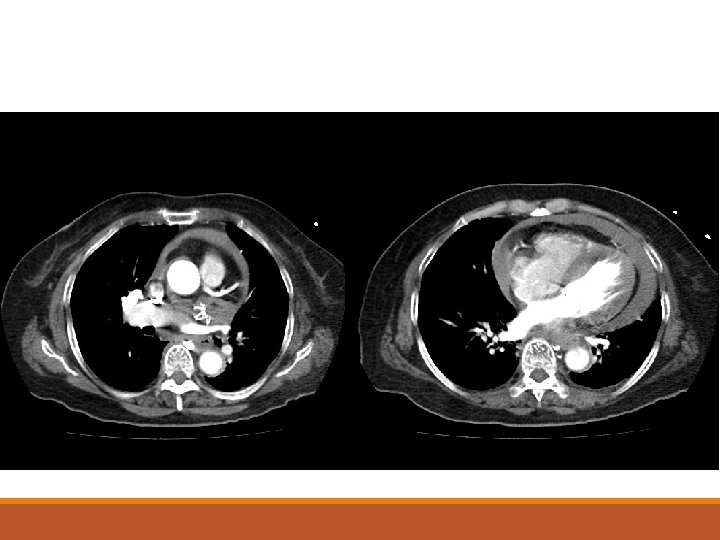

Contrast CT thorax is done after hemodynamic stability is restored:

5. I) What is the overall diagnosis of this lady? 6. What is the initial treatment of choice?

7. Name 3 risk factors for this condition.